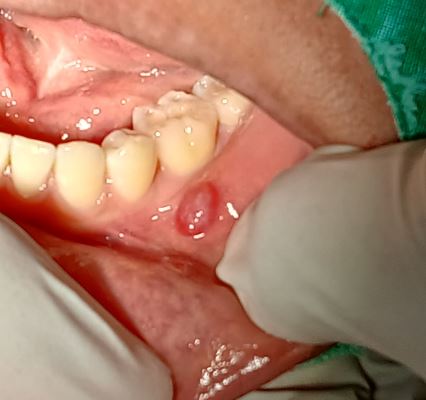

볼 안쪽 섬유종 제거

볼 안쪽 섬유종 제거입니다.

구강외과 전문의가 수술합니다.